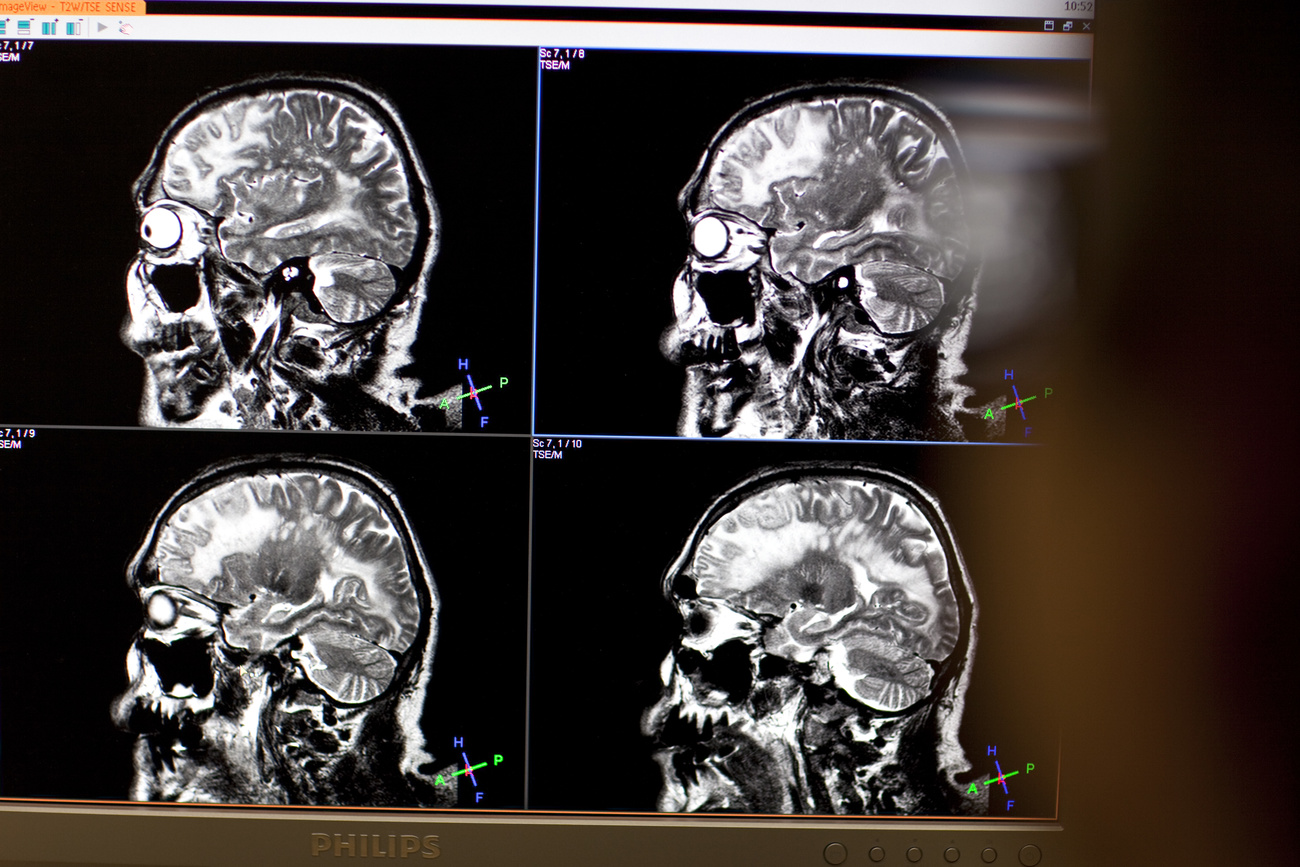

Il cervello e la medicina di genere

Uomini e donne non sono uguali nei sintomi, nell'incidenza e nella risposta alle cure di diverse malattie. È il tema di cui occupa la medicina di genere che analizza anche pregiudizi e generalizzazioni legate alle patologie, anche quelle cerebrali.

“Quello che noi sappiamo -spiega la medica- è che sia dal punto di vista del codice genetico, dunque del DNA, sia dell’ambiente e dello stile di vita vi sono delle differenze tra uomini e donne per certe patologie, non soltanto in termini di numero, quindi di incidenza e prevalenza di una malattia, ma anche per quanto riguarda il modo in cui la malattia progredisce e viene diagnosticata e deve poi anche essere curata”. È noto che le donne soffrono più frequentemente della malattia di Alzheimer, ma anche di depressione, ansia, emicrania, sclerosi multipla, gli uomini invece del morbo di Parkinson.